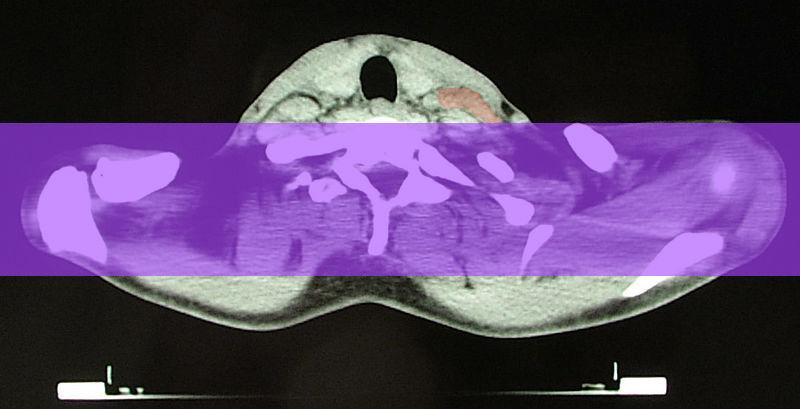

Wer im Bereich des Mediastinums (Mittelfeld zwischen den beiden Lungenhälften) bestrahlt wurde, hat das höchste Risiko, an den oben genannten Herzschädigungen zu erkranken.